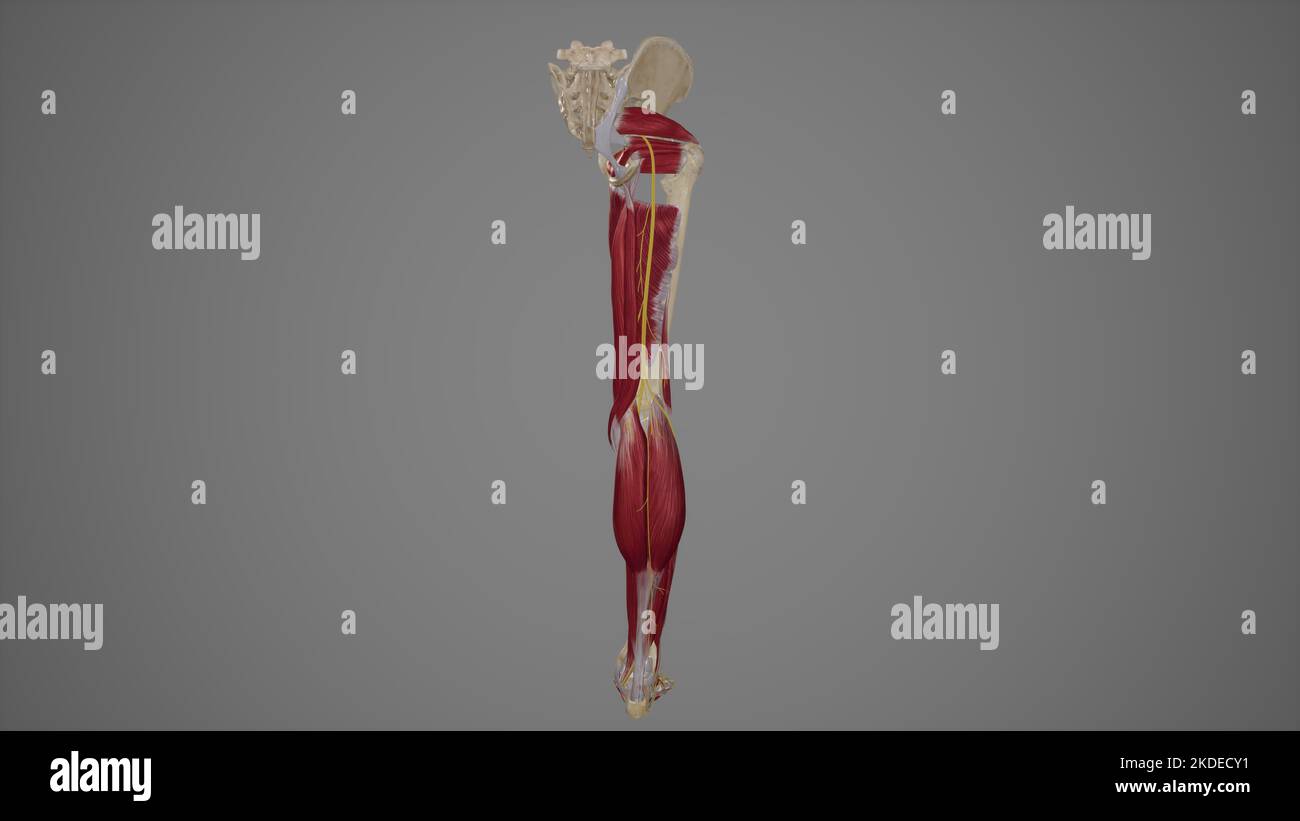

Illustration anatomique du nerf sciatique Banque D'Imageshttps://www.alamyimages.fr/image-license-details/?v=1https://www.alamyimages.fr/illustration-anatomique-du-nerf-sciatique-image490198325.html

Illustration anatomique du nerf sciatique Banque D'Imageshttps://www.alamyimages.fr/image-license-details/?v=1https://www.alamyimages.fr/illustration-anatomique-du-nerf-sciatique-image490198325.htmlRF2KDECY1–Illustration anatomique du nerf sciatique